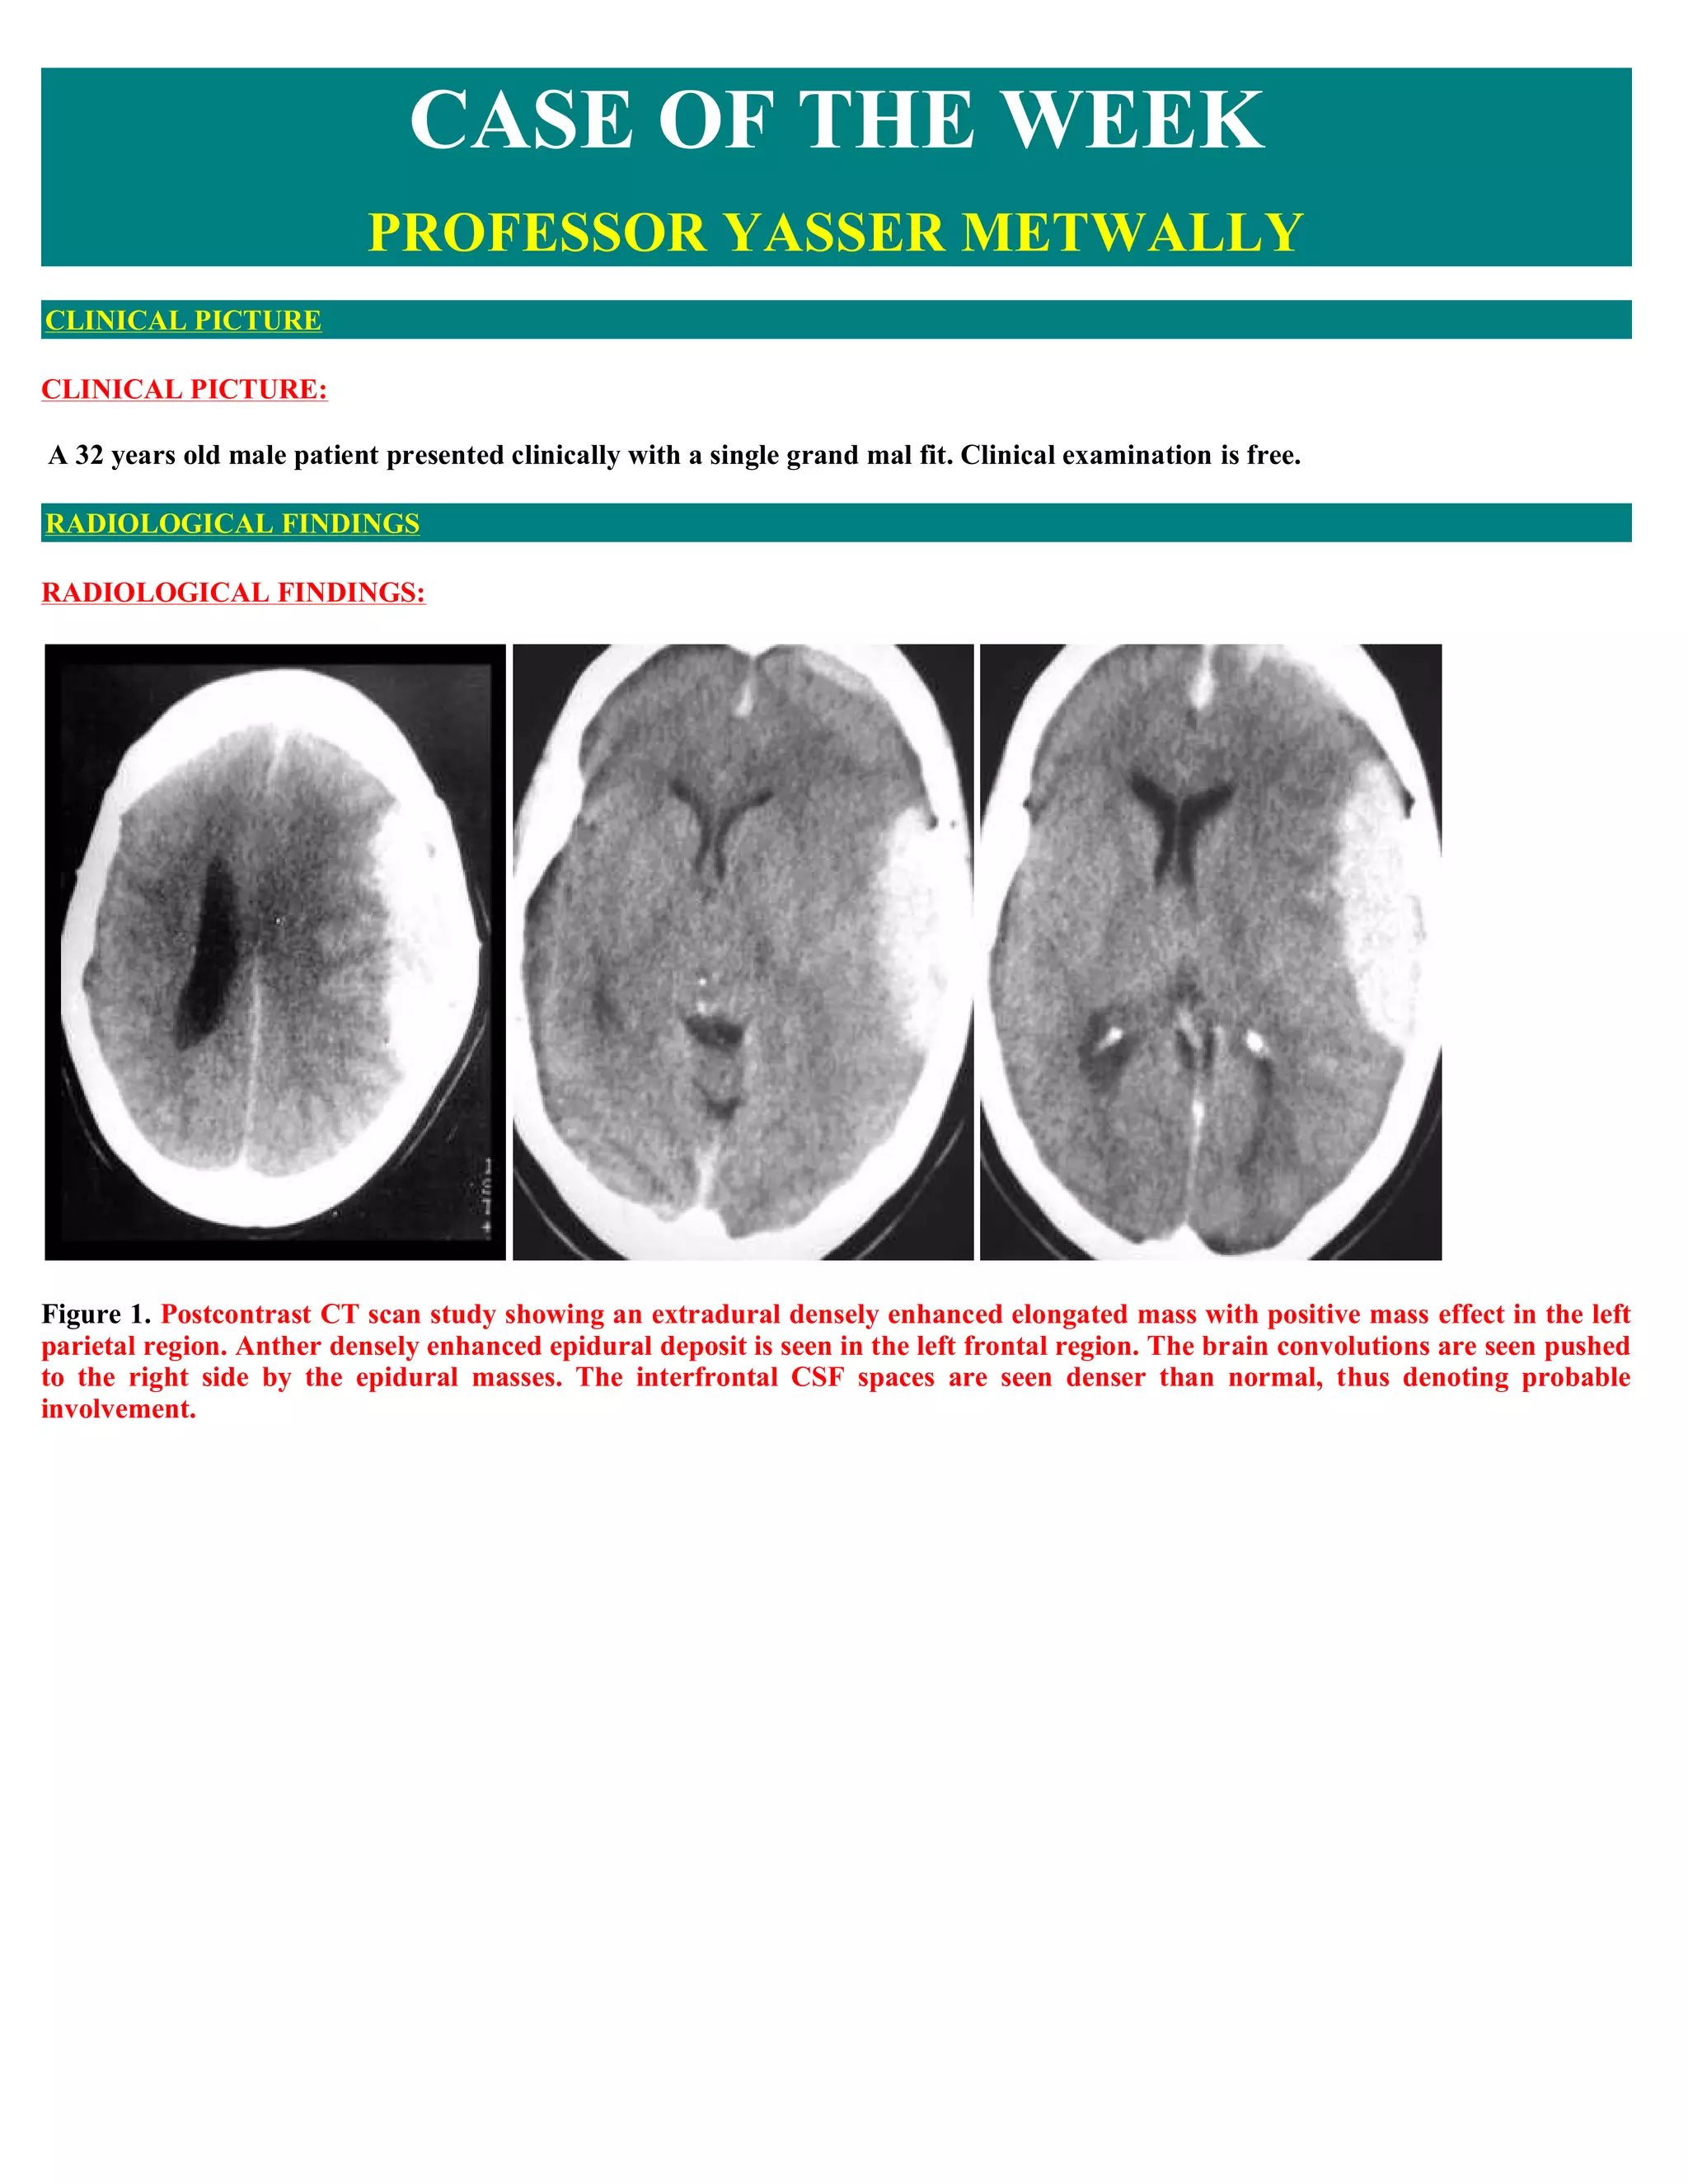

A 32-year-old male presented with a single grand mal seizure. CT scans showed extradural masses in the left parietal and frontal regions, compressing the brain and ventricles. Surgery revealed nodular dural thickening without brain infiltration. Biopsy diagnosed non-Hodgkin B-cell lymphoma. Further staging found extensive extraneural disease, though the CNS manifestations were the initial presentation. The patient was referred for oncology management for epidural secondary CNS lymphoma.